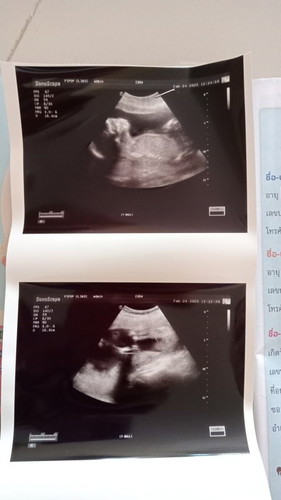

ทีมมิถุนาจร้า วันนี้ไปซาวด์มาแล้วดีใจมากๆเมื่อคุณหมอบอกเป็นผู้หญิงจนลืมถามน้ำหนักไปเลย